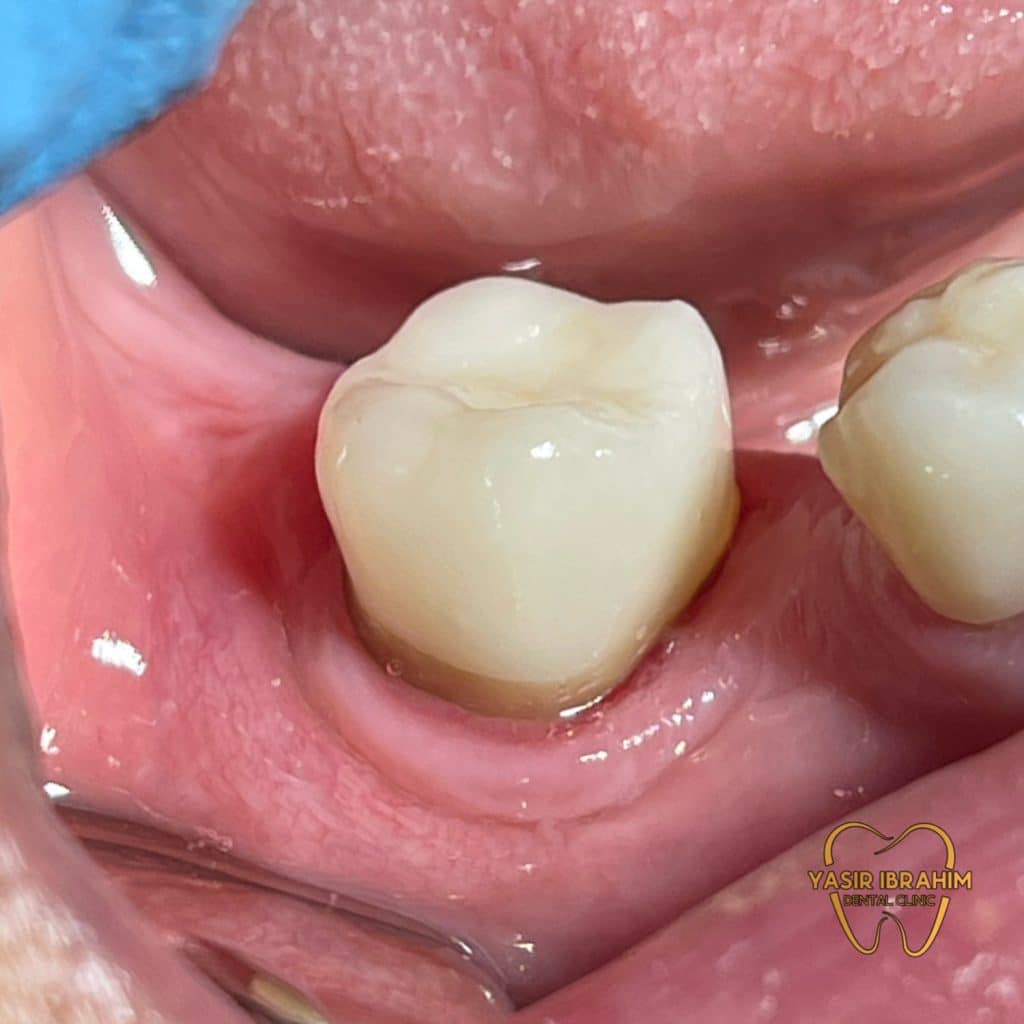

Tooth prep for endocrown with ferrule design.

ips e.max press.

Marginal adaptation.

endocrown cementation .